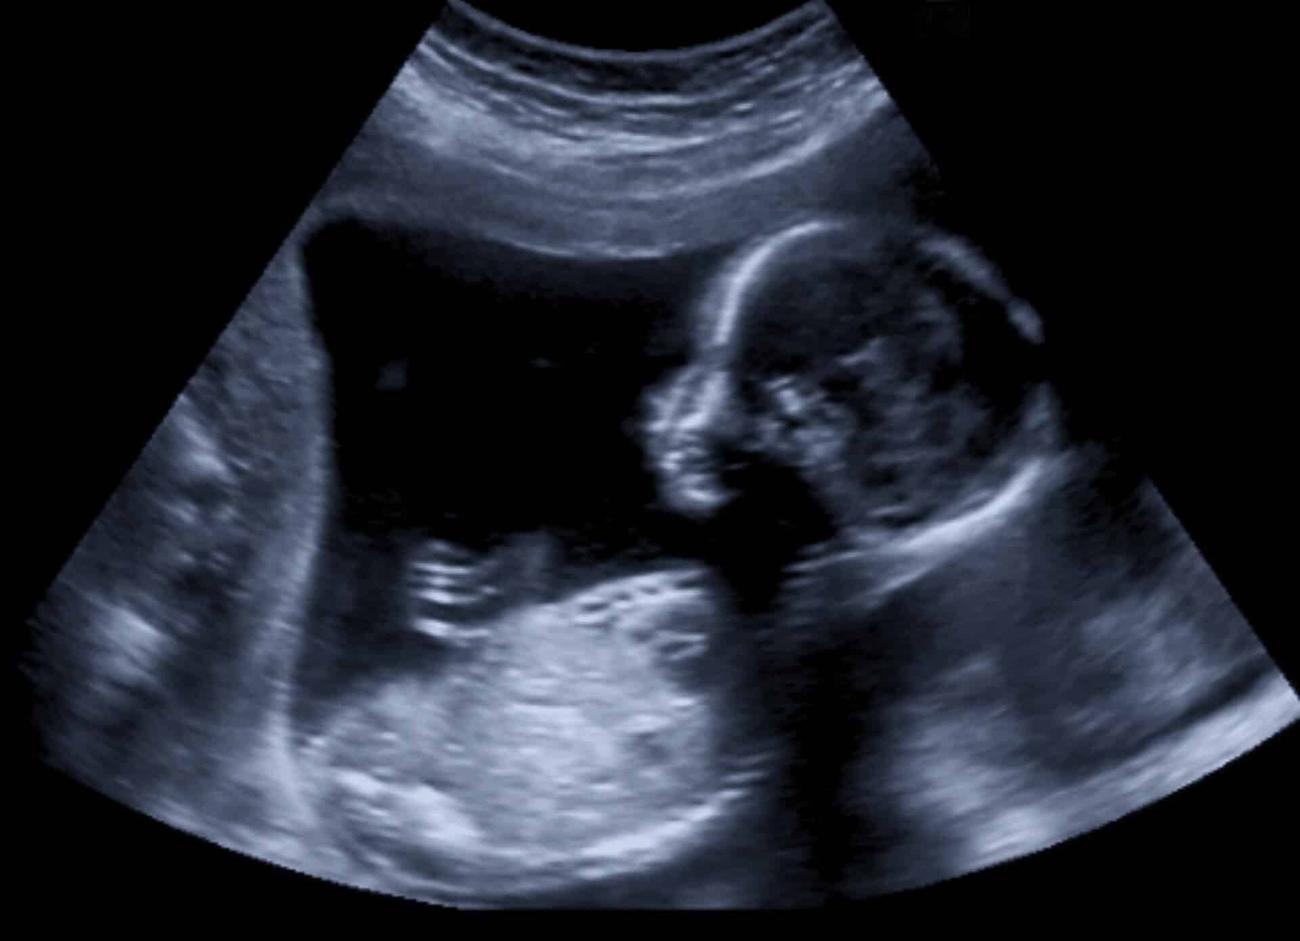

Η πρώτη τεχνητή μήτρα που θα μπορεί να φιλοξενήσει ανθρώπινο βρέφος θα φτάσει ένα βήμα πιο κοντά στην πραγματικότητα την επόμενη εβδομάδα. Πρόκειται για ένα επιστημονικό ορόσημο που θα μπορούσε να προσφέρει ελπίδα για τα χιλιάδες εξαιρετικά πρόωρα μωρά που γεννιούνται στις ΗΠΑ και ανά τον κόσμο κάθε χρόνο.

Η συσκευή της Vitara Biomedical ονομάζεται σύστημα EXTEND, συντομογραφία του EXTra-uterine Environment for Neonatal Development. Στην ανθρώπινη μήτρα, ένα έμβρυο παίρνει όλη τη διατροφή και το οξυγόνο που χρειάζεται μέσω του ομφάλιου λώρου που συνδέεται με τον πλακούντα. Η συσκευή EXTEND, που προορίζεται για βρέφη που γεννιούνται σε λιγότερο από 28 εβδομάδες κύησης, στοχεύει να μιμηθεί αυτές τις καταστάσεις.

Η μετάβαση από μια ανθρώπινη μήτρα σε μια τεχνητή μήτρα πρέπει να είναι απρόσκοπτη προκειμένου να σταματήσει η φυσική διαδικασία του εμβρύου να μετατραπεί σε νεογνό. Έτσι, κατά τη διάρκεια μιας καισαρικής τομής, οι σωλήνες εισάγονται στα ομφαλικά αιμοφόρα αγγεία και το βρέφος βυθίζεται αμέσως σε έναν βιοσάκο, έναν λοβό γεμάτο με ένα αποστειρωμένο υγρό αμνιακού τύπου. Οι σωλήνες που συνδέονται με την κυκλοφορία του αίματος του βρέφους, που ονομάζονται ομφαλικοί καθετήρες, παρέχουν τροφή. Ένα μηχάνημα που ονομάζεται οξυγονωτής εξωτερικής μεμβράνης παρέχει οξυγόνο.